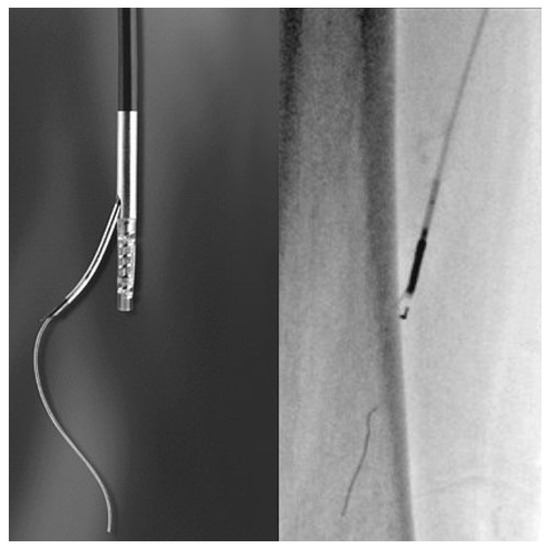

Septal Reduction Therapy for Hypertrophic Obstructive Cardiomyopathy

by Amir-Ali Fassa and Ulrich Sigwart

Cardiovasc. Med. 2010, 13(7), 228; https://doi.org/10.4414/cvm.2010.01519 - 11 Aug 2010

Cited by 2 | Viewed by 56

Hypertrophic obstructive cardiomyopathy can cause symptoms such as dyspnoea, angina pectoris and syncope. First-line pharmacological therapy includes betablockers, verapamil and disopyramid. However, 5–10% of patients with left ventricular outflow tract gradient are unresponsive to medical treatment. Therapeutic options for patients with drug-resistant symptoms [...] Read more.

Hypertrophic obstructive cardiomyopathy can cause symptoms such as dyspnoea, angina pectoris and syncope. First-line pharmacological therapy includes betablockers, verapamil and disopyramid. However, 5–10% of patients with left ventricular outflow tract gradient are unresponsive to medical treatment. Therapeutic options for patients with drug-resistant symptoms include surgical myectomy (SM) and alcohol septal ablation (ASA). The former has been performed for more than 50 years and involves surgical resection of the basal septum. The latter, which was proposed as an alternative to surgical therapy 15 years ago, is a catheter-based technique involving selective injection of ethanol in a septal coronary artery to induce a scar at the level of the basal septum. Both procedures are associated with excellent symptom relief and long-term survival. Complication rates are also comparable, although complete heart block requiring permanent pacemaker implantation tends to occur more frequently following ASA. Moreover, SM and ASA have never been compared by a randomised controlled trial. The choice of treatment should therfore be based on local availability and expertise as well as patient’s preference and associated conditions, taking into account the benefits and limitations of both techniques. Full article

Show Figures

Figure 1